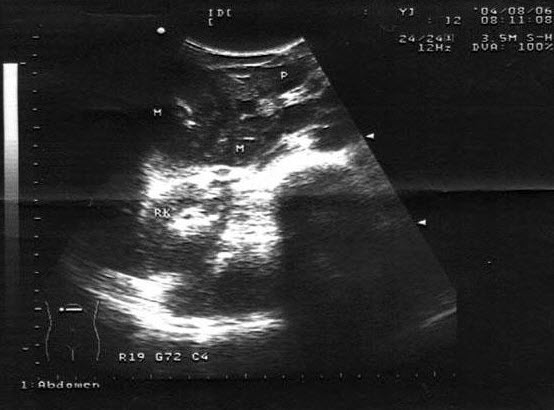

8、单项选择题

患者,女,35岁,有急性胰腺炎病史,现感上腹不适。结合中上腹超声声像图表现,诊断是()

A.胰腺占位并胰管扩张

B.急性胰腺炎

C.慢性胰腺炎并胰管结石

D.胆总管结石

E.胰腺癌